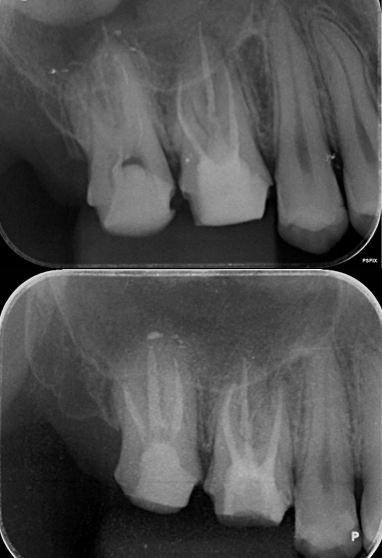

[池袋 歯医者]その歯、まだ残せるかもしれません

[池袋 歯医者]インプラントやセラミック治療の前...

[池袋 歯医者]サイナスリフトを回避できる?低侵...